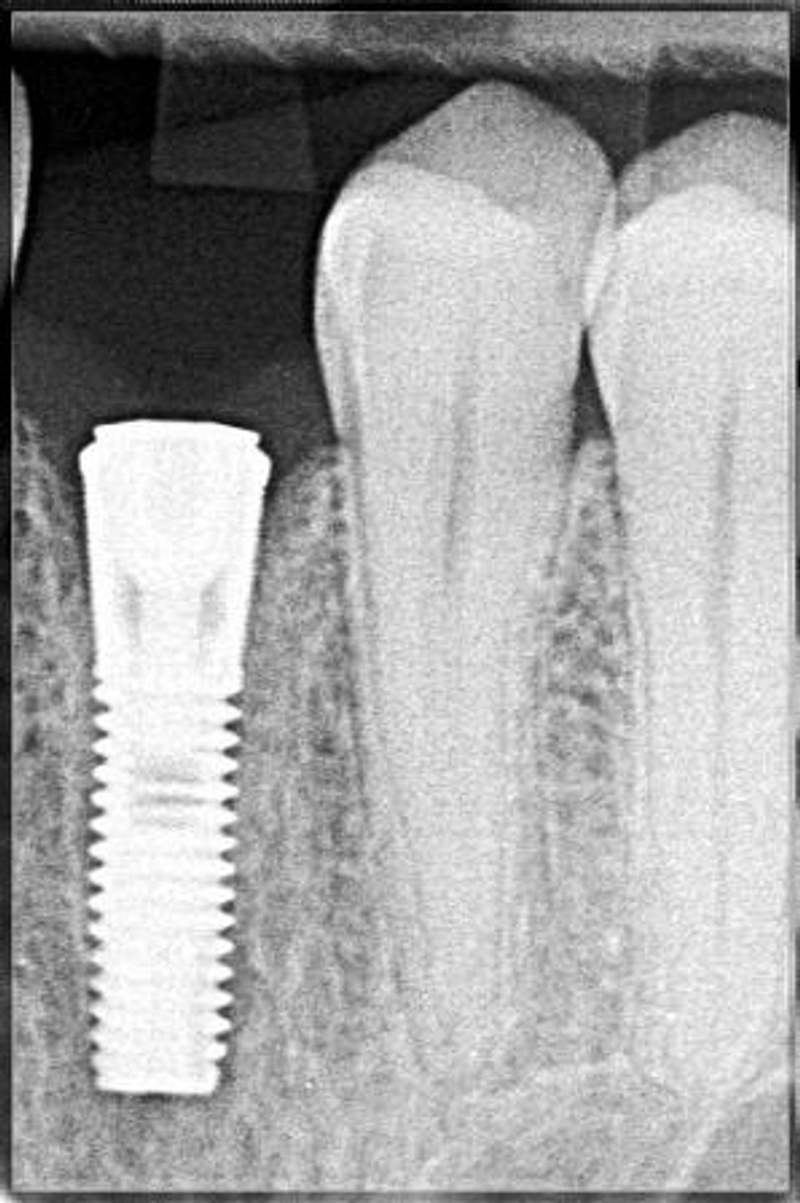

Имплантат служит или не служит. Срок службы заканчивается когда происходит потеря имплантат. Основным осложнением при имплантации является периимплантит .8 лет службы имплантатов-хороший результат. Фактически "живут" больше......и что делать с вышедшим сроком службы имплантатом? Мне бы хотелось себе поставить - собираюсь начать работу по этому вопросу в этом году, но хотелось бы представлять - а что дальше, что потом? Спасибо.